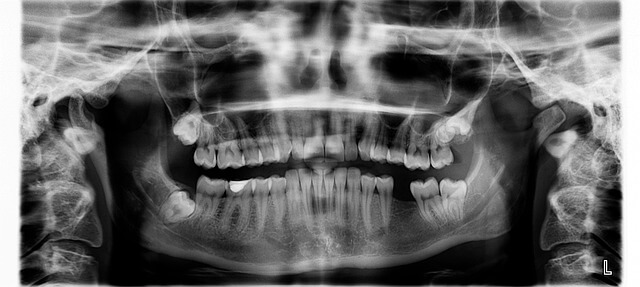

- * 1-1. 접수와 진단: 병원 방문 시 기본 검사인 엑스레이와 상담은 10~15분 소요됩니다.